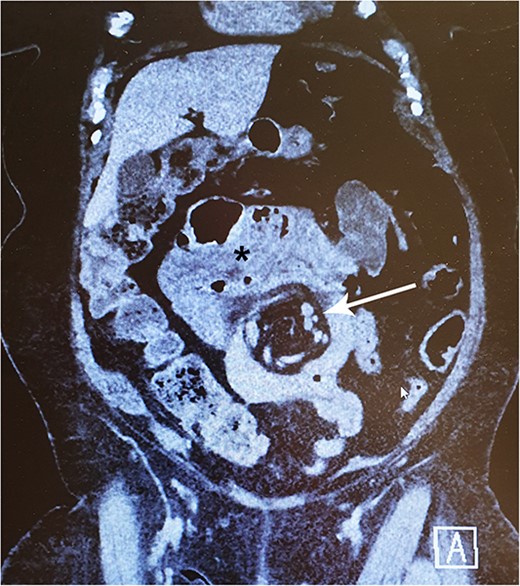

In late 2022, this now 77-year-old patient came to the emergency ward with intense abdominal pain. She had been experiencing transient colicky epigastric pain infrequently for the past few years. At this time, her medical history included hypertension, musculoskeletal disorders, diverticulosis, and a deep vein thrombosis in 2015. She took a daily multivitamin supplement and additional zinc, vitamin C and D, and received vitamin B12 injections every 3 months. A computed tomography (CT) scan revealed a suspicion of IH with a typical swirl sign in the mesenteric vascular structures (Fig. 1). There were no signs of compromised bowel blood perfusion or dilatation in the bowels or stomach. At the time, the exact procedure the patient had undergone 31 years earlier was unclear. The symptoms resolved quickly, and the emergency operation was not necessary. At follow-up, the patient remained symptom-free. Archived medical records revealed that she had undergone a JIB in 1991. In agreement with the patient, we proceeded with exploratory laparoscopy.

A 77-year-old woman with a history of jejunoileal bypass 31 years ago presented with intermittent colicky upper abdominal pain for 1–2 years. A rather painful episode led to hospital admission and CT scan, which showed a mesenteric swirl sign (arrow). Symptoms quickly subsided. Although she remained symptomless after that particular episode, an exploratory laparoscopy converted to laparotomy was performed 5 months later. This revealed a large mesenterial defect under the jejunoileal anastomosis. 390 cm of bypassed small bowel was found to be atrophied and packed with adhesions. This finding may be visible on CT scan (*).